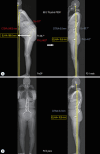

In adult spinal deformity (ASD) surgery, mechanical failure (MF) has been a significant concern for spine surgeons as well as patients. Despite earnest endeavors to prevent MF, the absence of a definitive consensus persists, owing to the intricate interplay of multifarious factors associated with this complication. Previous approaches centered around global spinal alignment have yielded limited success in entirely forestalling MF. These methodologies, albeit valuable, exhibited limitations by neglecting to encompass global balance and compensatory mechanisms within their purview. In response to this concern, an in-depth comprehension of global balance and compensatory mechanisms emerges as imperative. In this discourse, the center of gravity and the gravity line are gaining attention in recent investigations pertaining to global balance. This narrative review aims to provide an overview of the global balance and a comprehensive understanding of related concepts and knowledge. Moreover, it delves into the clinical ramifications of the contemporary optimal correction paradigm to furnish an encompassing understanding of global balance and the current optimal correction strategies within the context of ASD surgery. By doing so, it endeavors to furnish spine surgeons with a guiding compass, enriching their decision-making process as they navigate the intricate terrain of ASD surgical interventions.